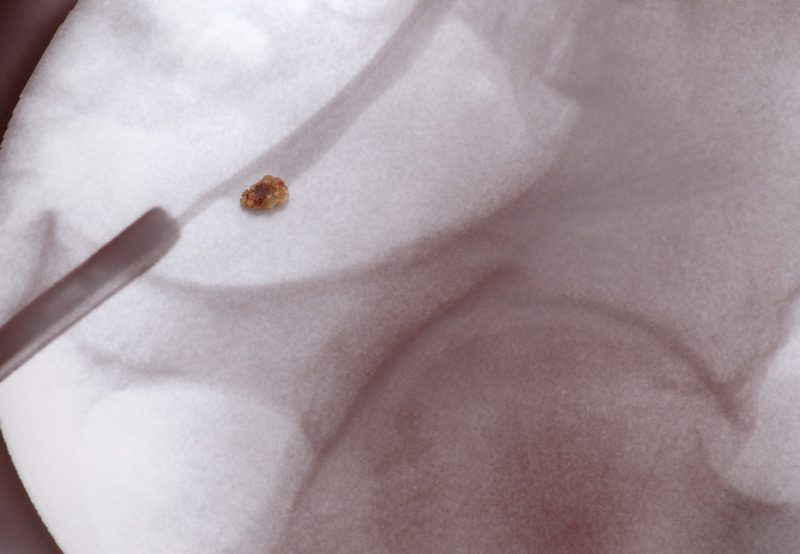

Nephrolithotomy

Shockwave

Ureteroscopy